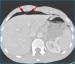

Abbildung 3: Lungenfenster Die Rekonstruktion der CT-Bilder im sogenannten "Lungenfenster" zeigt anschaulich die Luftansammlungen in der Peritonealhöhle. Das Ligamentum falciforme der Leber ist von Luft umgeben (Pfeile). |

Die Rekonstruktion der CT-Bilder im sogenannten "Lungenfenster" zeigt anschaulich die Luftansammlungen in der Peritonealhöhle. Das Ligamentum falciforme der Leber ist von Luft umgeben (Pfeile). |